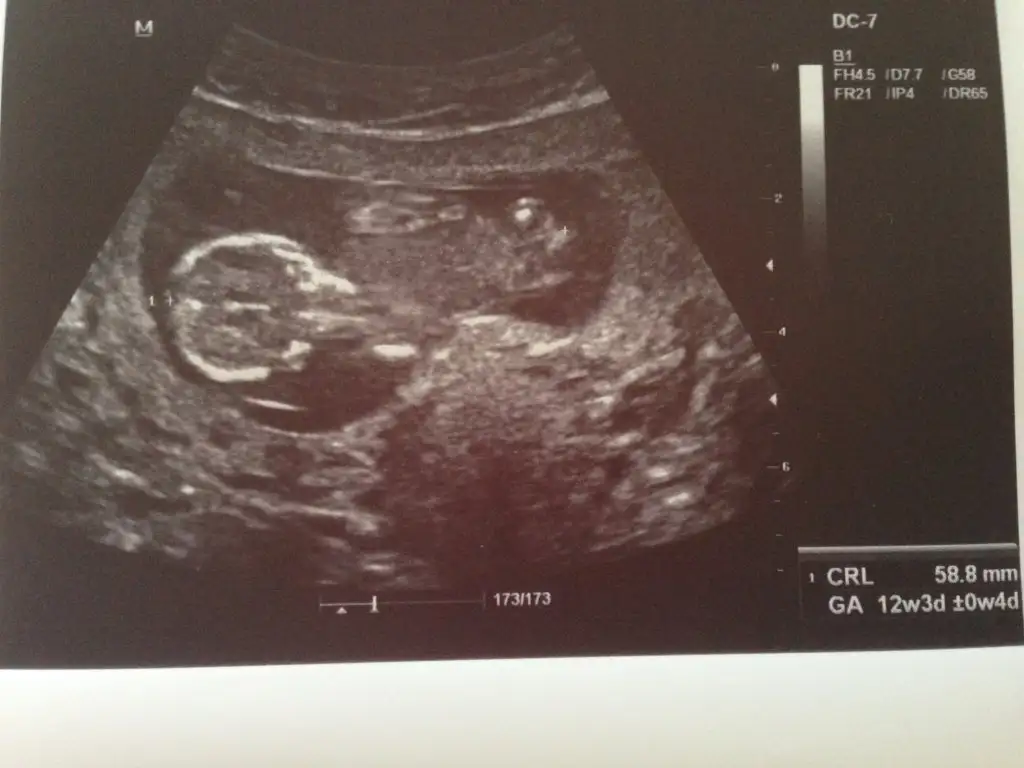

Evveet teyzoşlarıı yorumları alalım bu arada ikiz olduğu için orda iki bebek var ama bende hangisi 1 hangisi 2 bilmiyorum

Yaaa ben şimdi burdan ne alayim ki? :/ 12+3 bu ama bişey belli diyil ki. Siz anlarmisiniz anneler? :)